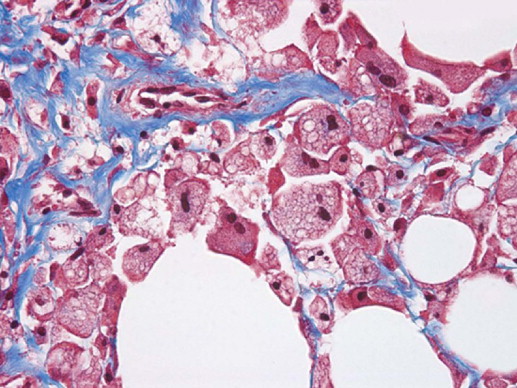

The disruption of adipocyte cells send chemotactic signals that activate the body’s inflammatory mechanisms, attracting macrophage cells to the area to engulf the lipids and cell debris. Histology taken 1 month post-procedure confirms the process of adipocyte clearance ( Figure 12.3 ). The macrophages migrate to the lymphatic system and on to the liver where the lipids are processed through normal biochemical pathways. This results in a reduction in adipose tissue volume in the treated area.